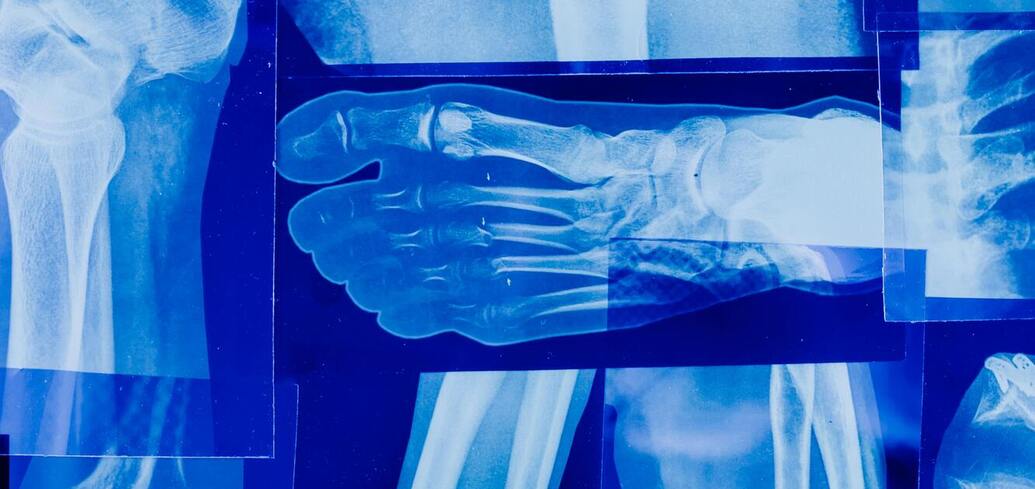

Менопауза приводит к гормональным изменениям, которые могут ослабить женские кости, повышая риск переломов. Снижение уровня эстрогена во время этой фазы способствует потере костной массы и потенциальному развитию остеопороза.

Хотя, как рассказывает News Bytes, восстановить плотность костной ткани, как у молодости, невозможно, здоровые привычки могут замедлить быстрое истончение костей. Вот несколько стратегий, которые помогут предотвратить потерю костной массы.